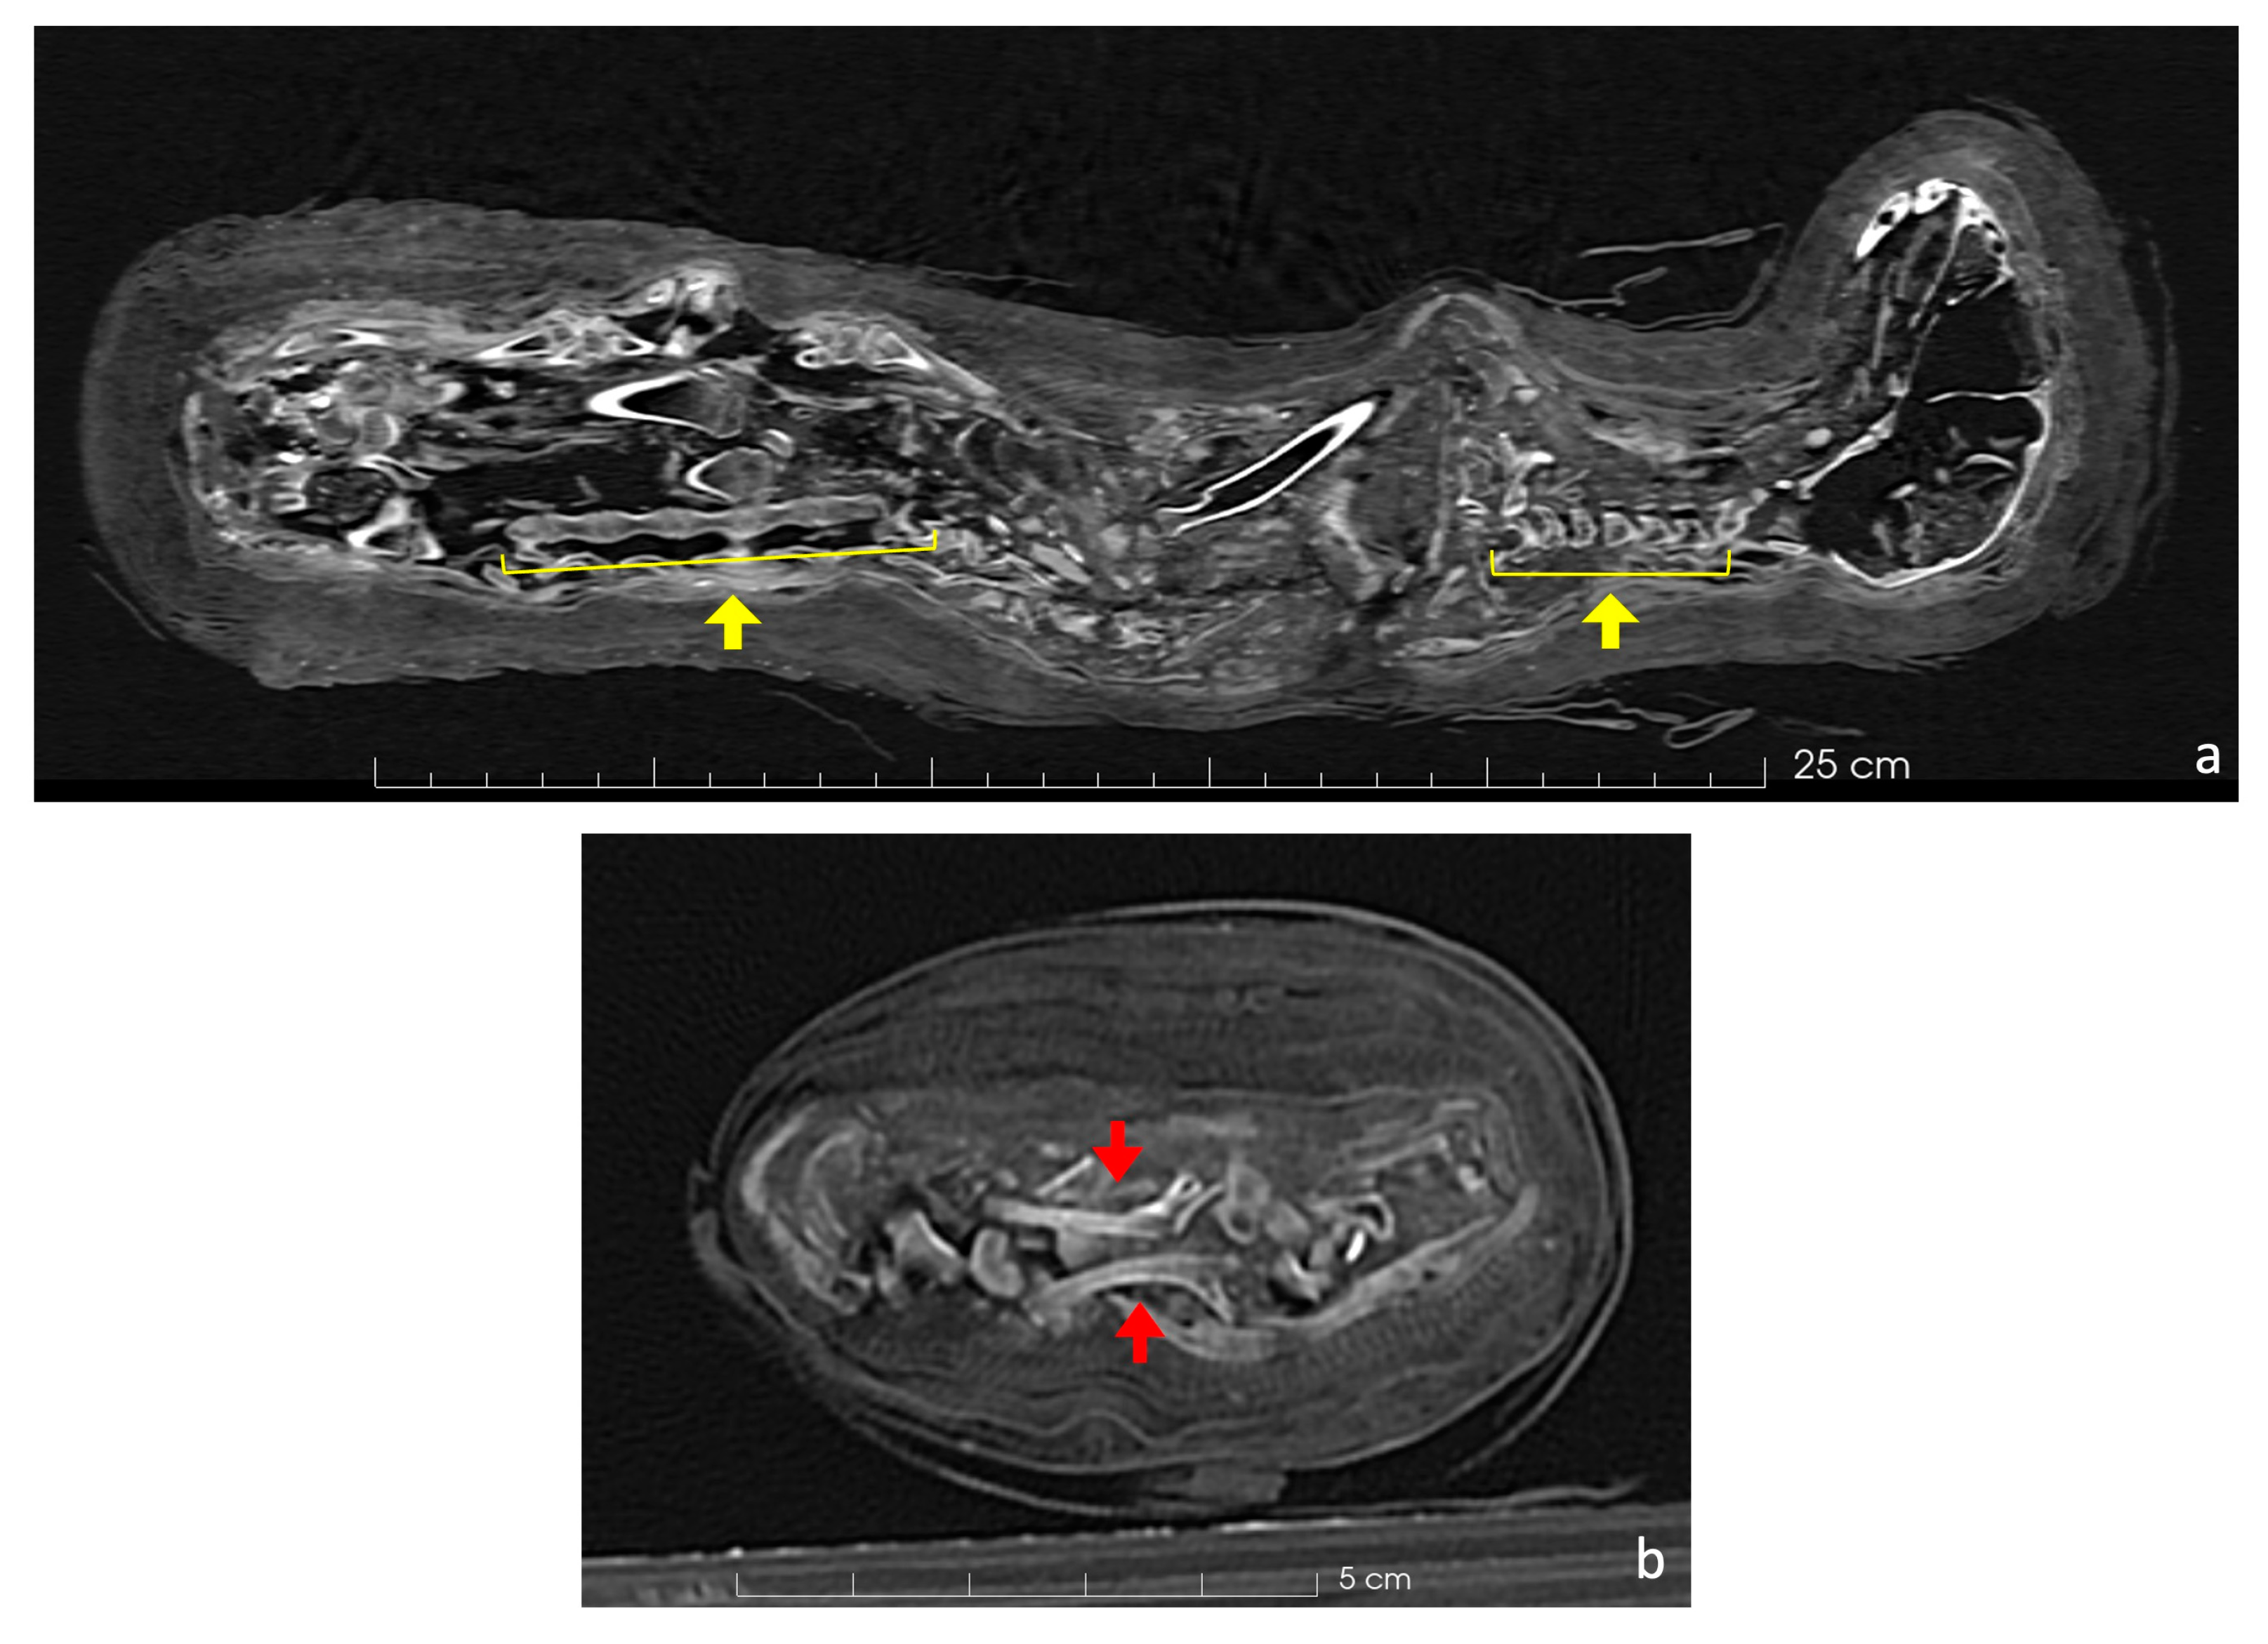

The scans revealed unerupted permanent teeth within both the mandible and maxilla (Figure 3). The canines shown in the figure are deciduous, and the permanent teeth have yet to erupt. In the maxilla, the fourth premolar remains unerupted (Figure 3a), while in the mandible, the first molar is still inside its chamber (Figure 3b). This helps in establishing the age at death.

Figure 3.

Axial CT scan of the cat’s dentition. (a) The unerupted fourth premolar in the maxilla is indicated by a red arrow. (b) The molar in the mandible remains enclosed within its chamber (red arrow). (c) 3D rendering of the skull and mandibles with the gems of the upper fourth premolar (in purple) and lower first molar (in blue) still in the alveoli.

The scans show that the distal epiphyses of the femurs were unfused, as were the proximal epiphyses of the tibiae (Figure 8). Regarding the forelimbs, the proximal epiphyses of the right humerus and the right ulna were unfused, as well as the distal epiphysis of the right radius. All these findings are an indicator of an immature individual [42,43]. The young age is a problem for its taxonomic identification, as the diagnostic skeletal features are not fully developed and biometry is limited to certain skeletal elements. The distal breadth of the humerus (Bd, following von den Driesch, 1979) is 15.8 mm. The humerus was chosen as the distal epiphyses was already fully ossified. Even if a possible slight further growth of the bone cannot be excluded, the size is in line with the variation of Felis silvestris and looks to be too small for the jungle cat Felis chaus [14]. The size overlaps with that of the sand cat Felis margarita [14], but this species is considered to be much rarer and looks to be uncommon in the zooarcheological record in Egypt [16]. If we hypothesize the attribution to Felis silvestris, common amongst votive mummies [47,48], the individual was almost certainly younger than 9 months [43,44]. Furthermore, the dentition was still composed of deciduous teeth, while the permanent molars were unerupted (Figure 3b) and the fourth premolar of the maxilla was still within the chamber (Figure 3a). Since molars erupt at 5 or 6 months, and the eruption of permanent premolars occurs between 4 and 6 months [45], it is possible to hypothesize that the animal was probably less than about 5 months old at death. This age is very common among cat mummies, as other mummies prove [47,48,50].